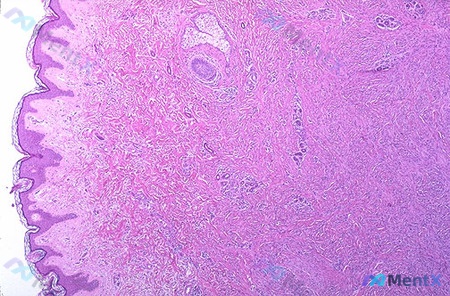

整理到一份有争议的皮肤病理读片资料,先抛核心信息: > 病理描述:上真皮层,血管周围和毛囊周围可见红细胞外渗(标注a)、含铁血黄素细胞(标注b)。 之前的读片里还提到了「非典型细胞、核仁明显、浸润性生长、促结缔组织增生」,甚至倾向了恶性肿瘤方向。 但如果只看用户明确给出的核心描述——「上真皮层+血管...